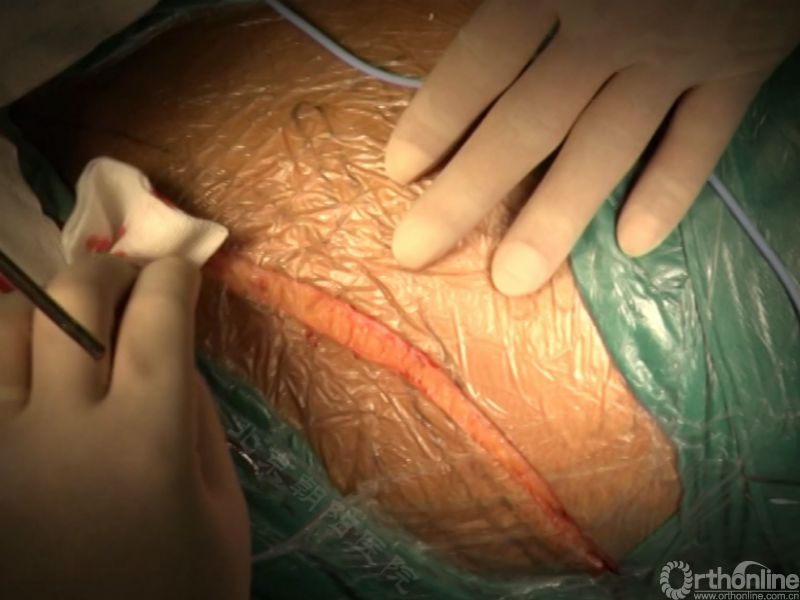

图12.前路矫正术体位摆放示例

胸腰段/腰段AIS前路矫正手术示例

患者11岁青少年女性,诊断为Lenke 5C型AIS,T10-L4 Cobb角50.5°、T5-10 Cobb角31.5°,主弯顶椎为L1,融合范围选择为T1-L3。

术者:首都医科大学附属北京朝阳医院骨科 海涌教授

经近端需内固定的椎体(T11)相对应的肋骨表面做一弧形切口,分离浅层软组织直至肋骨表面的多层肌肉组织,切口止于脐的远端偏外侧。

骨膜下环形剥离完整显露肋骨。